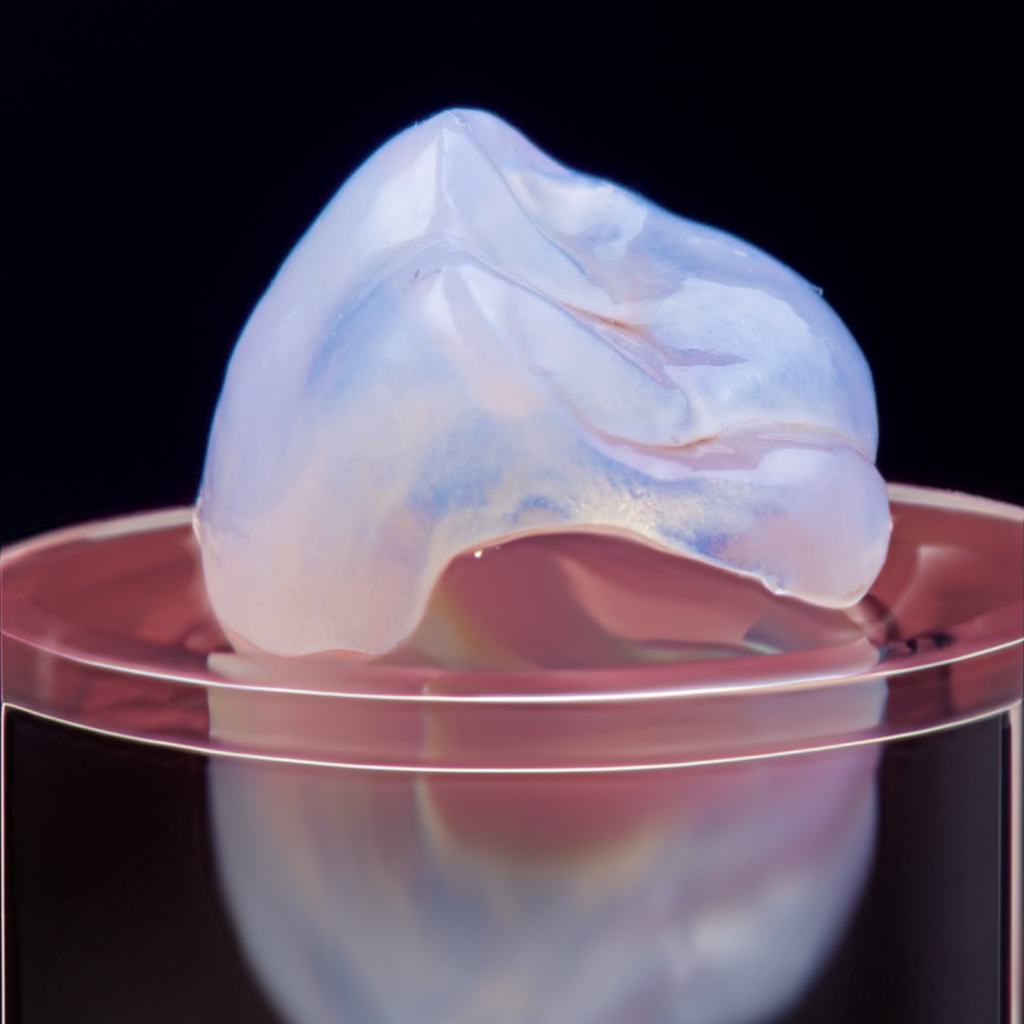

CeraCap

Restore your natural bite

세라캡은 어떤 치료인가요?

씹는 힘이 강하거나, 잘 때 이를 악무는 습관, 이갈이로 인해

어금니의 교두가 다 갈려서 씹는 면이 바닥처럼 평평해진 상태를

갈리기 전 교합면 모양으로 교두를 살려 복원하는 치료입니다.

교두를 살려 복원하는 치료

씹는 힘이 강하거나, 잘 때 이를 악무는 습관, 이갈이로 인해 어금니의 교두가 다 갈려서 씹는 면이 바닥처럼 평평해진 상태를 갈리기 전 교합면 모양으로 교두를 살려 복원합니다. 크라운처럼 직사각형 형태로 몸통을 삭제하지 않고, 모자 씌우듯이 머리만 복원합니다.

세라믹 블록으로 제작

인레이·온레이 제작할 때와 동일한 세라믹 블록을 깎아서 만들기 때문에 씹어도 깨지지 않고 유지 관리에 편리합니다. 세라믹 블록을 밀링기에 돌려서 세라캡을 제작하며, 밀링기 기능이 치아를 적게 삭제할 수 있게 해주기 때문에 밀링기를 사용합니다.